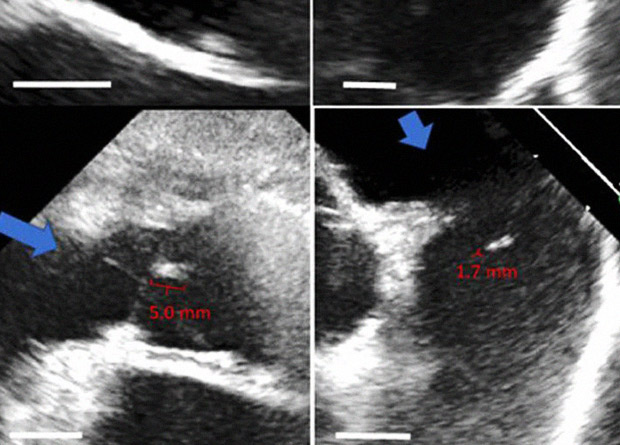

Биологи представили искусственные сердечные клапаны, которые могут расти вместе с сердцем. Такие имплантаты необходимы детям с пороками сердца: сейчас растущим пациентам приходится раз за разом переносить операции по замене клапанов. Ученые успешно протестировали имплантаты, полученные с помощью тканевой инженерии, на растущих ягнятах. Работа опубликована в Science Translational Medicine.

Команда биологов под руководством Роберта Транкилло (Robert Tranquillo) из Миннесотского университета уже не первый год ведет разработку новых сердечных клапанов, которые бы подстраивались под растущий детский организм. Для получения материала для клапанов исследователи предлагают выращивать в лабораторных условиях из фибробластов ткани, которые образовывают внеклеточный матрикс – сеть коллагеновых волокон. Клетки